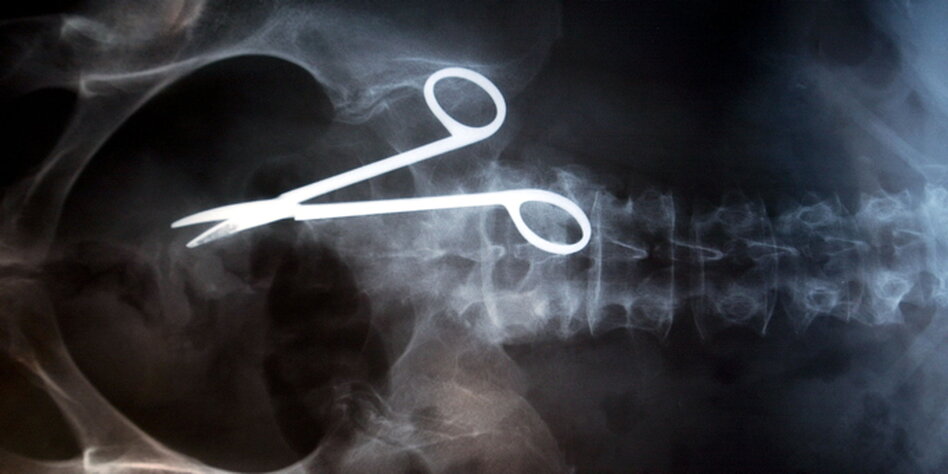

(IMG) Bild: Frage der Beweislast: Hier dürfte der Fall klar sein.

Nach wie vor müssten Betroffene – außer bei offensichtlichen Fehlern wie

falsch amputierten Gliedmaßen – beweisen, dass der Arzt einen Fehler

gemacht hat. Das könnten sie aber nicht, weil ihnen das Fachwissen fehle.